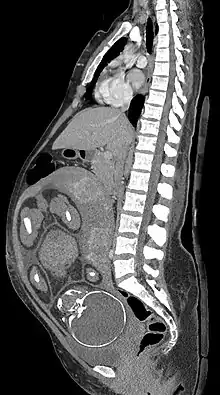

MRI is commonly used in pregnant women with acute abdominal pain and/or pelvic pain, or in suspected neurological disorders, placental diseases, tumors, infections, and/or cardiovascular diseases.[3] Appropriate use criteria by the American College of Radiology give a rating of ≥7 (usually appropriate) for non-contrast MRI for the following conditions: